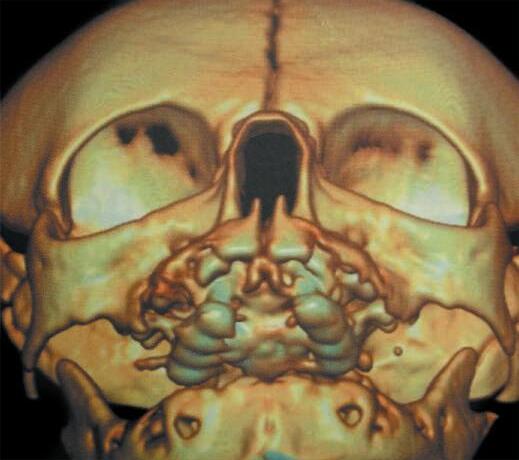

A tomografia computadorizada (TC) é o exame de escolha: valores abaixo de 11 mm são considerados sugestivos. Alguns autores mais rigorosos consideram o limite inferior de 8 mm (Fig. 1-1). A TC também avalia malformações associadas e estruturas como lâmina cribriforme e base do crânio.9 O diagnóstico diferencial deve incluir atresia de coanas, cistos, encefaloceles e tumores. A endoscopia nasal é útil para localização da obstrução.5,10

Além da correção esquelética, a ERM proporciona alargamento da base nasal, promovendo a redução da resistência ao fluxo aéreo e, consequentemente, aumento da ventilação nasal (Fig. 1-4).

9. Ao final da expansão, nova TC pode ser realizada para mensuração objetiva do ganho de espaço aéreo (Fig. 1-4), além da avaliação clínica (Fig. 1-8).

Apesar da eficácia da técnica de desgaste ósseo na abertura piriforme, seus potenciais riscos e complicações levaram ao aparecimento de outras opções terapêuticas. Vários estudos demonstraram que a atresia é maxilar, não se limitando ao piriforme, mas se estendendo por quase toda a cavidade óssea nasal.12,14 A expansão rápida da maxila, com dispositivo disjuntor e ancoragem esquelética por meio de miniparafusos, com sua fundamentação anatômica, biomecânica e funcional, é menos invasiva, proporciona uma expansão tridimensional eficaz ao longo de toda a fossa nasal, produzindo uma melhora funcional consistente nas vias aéreas superiores, que se mantém ao longo de todo o período de crescimento craniofacial (Fig. 1-9). Assim, a ERM credencia-se como técnica de escolha no tratamento da ECAP.15